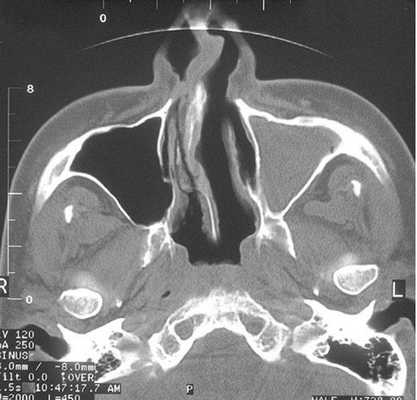

Тотальное заполнение жидкостью (кровью?) левой верхнечелюстной пазухи, повреждение носовой перегородки на компьютерной томограмме

Что показывает КТ пазух носа

Процедура КТ носа и околоносовых пазух дает возможность изучить строение анатомических структур и выявить особенности патологического процесса. Обследование рассматриваемой области на компьютерном томографе показывает:

деструктивные изменения и травматические повреждения лицевых костей;

утолщение слизистой оболочки носа и синусов;

искривление носовой перегородки;

воспаления внутри пазух (КТ покажет гайморит, фронтит, этмоидит, сфеноидит);

абсцессы носовой перегородки;

полипы, гранулемы, кисты слизистой оболочки воздухоносных полостей лицевого черепа;

опухоли в околоносовых пазухах;

скопление крови, экссудата, гноя в синусах;

инородные тела в носовых ходах и костных углублениях;

кровоизлияния в пазухи и мягкие ткани;

стоматологические патологии (врастание корня или смещение зуба в гайморову пазуху);